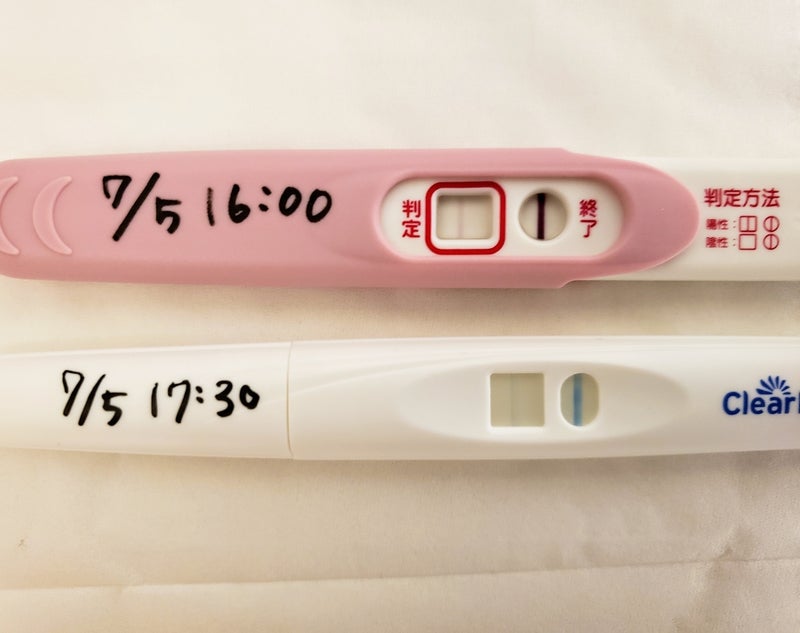

May 15, 21 · :妊娠検査薬の反応(陽性&陰性) 生理予定日が6月8日(ルナルナのアプリでは)でしたが、まだ来ていません。 排卵検査薬をすると濃い反応がでました。Feb 27, 18 · なので、妊娠検査薬のフライングをするなら早くても高温期8日目以降が良いと思います。 6日目、7日目は出ないと分かっていても、陰性だったときに落ち込みます(>_Jul , · アラフォー不妊治療27 中国製の早期妊娠検査薬DAVID&クリアブルーで陽性 こんにちは! ゆとり主婦になりたいマリー( @yutori_shuhu )です。 38歳で始めた不妊治療の記録をさかのぼってブログにしています(この記事は年3月時点のお話です)。 通院1回

Jul 05, 19 · こんにちは。saeです。私を一時期検索魔にさせた『フライング検査』について書いてみます。私もそうでしたが、みんなとても知りたい情報だと思うので「私の場合はこうでしたー!」を書いておきますね!私が使用したのは早期妊娠検査薬「妊娠しているかもし妊娠検査薬 陽性 tyuumarublogのブログ 21年06月08日 0853 年10月15日生理予定日から4日間遅れたため妊娠検薬で検査しました。 結果は・・・陽性判定! ! 急いで旦那にLINEしました (^^♪19年に一度初期流産しているため、嬉しい反面心配もいっぱいでしApr 10, 17 · 妊娠検査薬を一昨日使ったところ1分前後で、うっすらと陽性が出ました。2日頃から生理のような出血があったので(3日程で止まりました)蒸発線かなと思いましたが、時間が経っても消えていません。これは陽性と判断していいのでしょうか?

Oct 14, 16 · 人気の妊娠検査薬クリアブルー完全ガイド|いつから使える?フライング検査で蒸発線が出た私の体験談。陰性から陽性に変わる理由・出血中でも正しく判定できる?失敗しない検査方法で試した口コミ・写真・画像付きでどこよりも詳しく紹介します。Mar 05, 21 · 排卵検査薬ドゥーテストで排卵日を確認してみた陽性画像あり 最後に、私が実際に排卵日予測検査薬を使用して排卵日を確認した体験談をお伝えして終わりたいと思います。 aoi 排卵検査薬の実物画像が出てきますので、苦手な方はご注意くださいJan 25, 21 · 医師監修妊娠検査薬の陽性判定が薄い場合があります。この場合は正しい妊娠検査薬使い方をしたなら妊娠している可能性があります。しかし使い方によっては蒸発線と呼ばれる陽性判定に似た薄い線が現れることがあります。線が蒸発線なら妊娠していません。